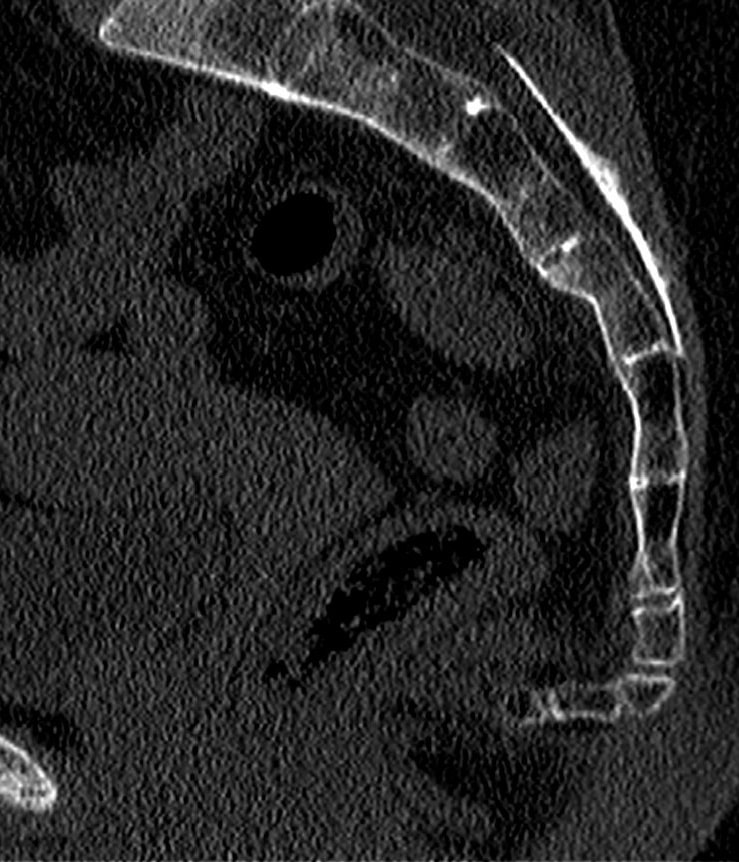

Рентгеновские снимки крестцово-копчикового отдела позвоночника